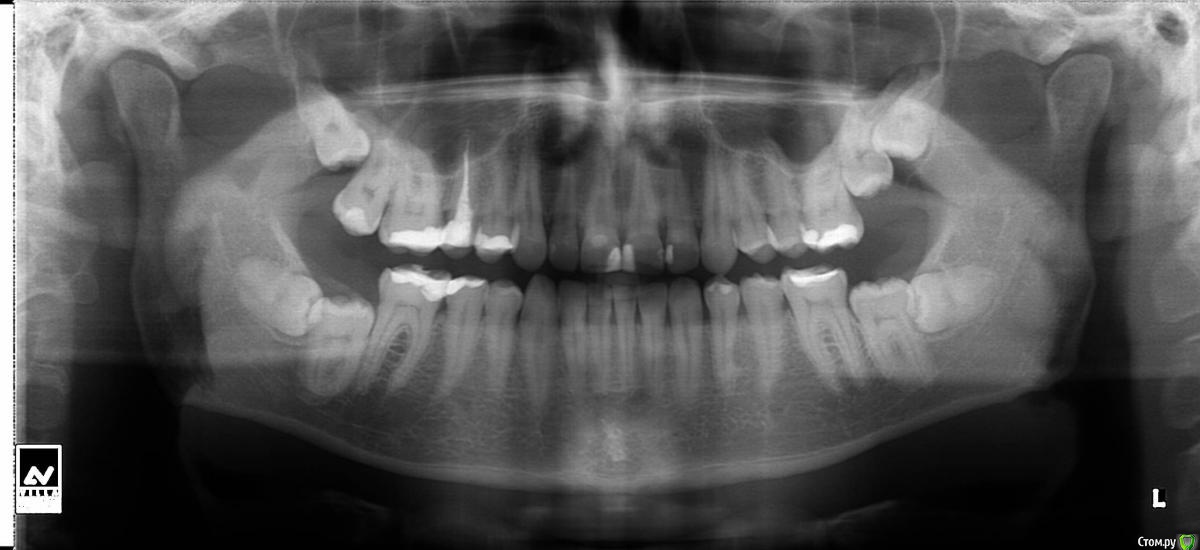

Чертков Александр Опубликовано 24 декабря, 2014 Поделиться Опубликовано 24 декабря, 2014 Доброго утра и спасибо за ответ! 1. Этот ответ мне нравится По поводу удлинения зубов вниз - пытались еще раньше. Проблемы с прикусом - я в итоге их (края) очень оперативно "съедаю", очень интересный прикус. 2.Можете, чуть-чуть поподробнее. Какие именно это будут проблемы? Ну а тут Вы вообще заинтриговали. и оставили в думах посерьезнее) С какого этапа бы начали Вы?Если детально оценить рентгенограмму, то видно, что 7е зубы в "полупрорезавшемся" положении, т.е. в полости рта их еще нет, но частичное их примыкание к задней поверхности 6х говорит о их непосредственном контакте со средой полости рта, соответственно вероятность проникновения микрофлоры к ним высока и риски кариеса и локального (местного) пародонтита тоже. По поводу "благополучного съедания" всего наращиваемого...это проблема прикуса, с него, а точнее с диагностики и надо начинать. А если уж прямым текстом, то нужны консультации ортодонта, ортопеда и хирурга. Предполагаемый план действий: удаление 8х, "вытягивание" 7х, восстановление правильного и естественного прикуса, а уж потом "эстетика", как логичное завершение. 1 Ссылка на комментарий

Mel18 Опубликовано 24 декабря, 2014 Автор Поделиться Опубликовано 24 декабря, 2014 Если детально оценить рентгенограмму, то видно, что 7е зубы в "полупрорезавшемся" положении, т.е. в полости рта их еще нет, но частичное их примыкание к задней поверхности 6х говорит о их непосредственном контакте со средой полости рта, соответственно вероятность проникновения микрофлоры к ним высока и риски кариеса и локального (местного) пародонтита тоже. По поводу "благополучного съедания" всего наращиваемого...это проблема прикуса, с него, а точнее с диагностики и надо начинать. А если уж прямым текстом, то нужны консультации ортодонта, ортопеда и хирурга. Предполагаемый план действий: удаление 8х, "вытягивание" 7х, восстановление правильного и естественного прикуса, а уж потом "эстетика", как логичное завершение. охх..вот это уже, безусловно, не самые радостные и ожидаемые действия! но я Вас услышал и непременно приму к сведению! Огромное спасибо! Ссылка на комментарий